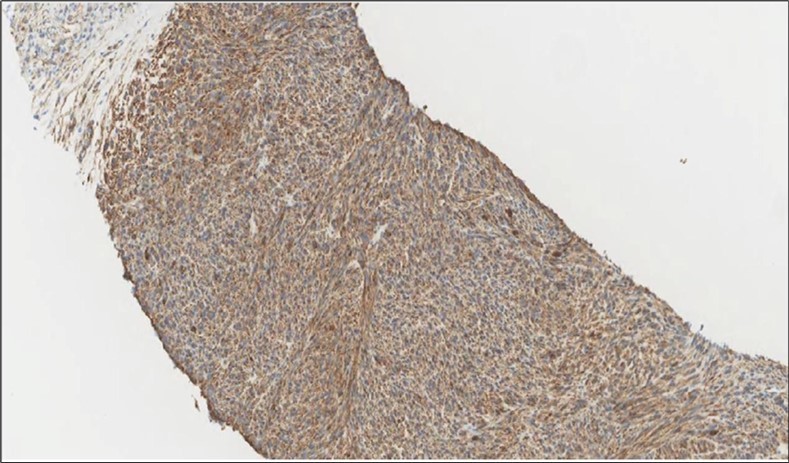

Figure 4.Left thyroid Cells are diffusely positive for Caldesmon immunohistochemistry (IHC, x200)

cancer, or other metastatic tumors without further testing with genetic or molecular studies 3, 7. Immunohistochemical testing plays a vital role in differentiating LMS from such similar tumors as it stains positive for vimentin and smooth muscle actin (SMA), and is variably positive for HHF35, desmin (50%-100%), and H-caldesmon 3, 6. Moreover, there were no reported cases where thyroid LMS stained positive for thyroglobulin, cytokeratin, calcitonin, chromogranin, or protein S100 3. Our patient’s left thyroid biopsy showed the characteristic microscopic features and was positive for SMA, desmin, caldesmon, P63 with patchy EMA (Figure 1, Figure 2, Figure 3, Figure 4) as well as her liver biopsy (Figure 5, Figure 6, Figure 7); whereas her right thyroid showed clear papillary thyroid cancer cell features (Figure 8, Figure 9).